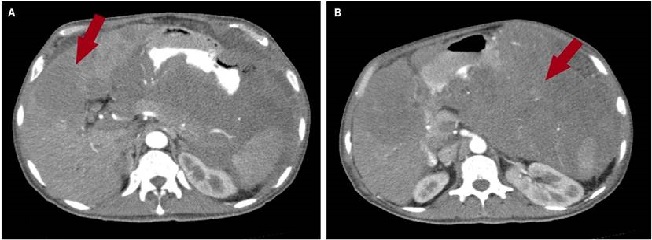

En la tomografía axial computarizada (TAC) de tórax se evidenciaba consolidación alveolar con infiltración en ambas bases pulmonares en vidrio deslustrado y engrosamiento septal (Figura 2). En la TAC de abdomen y pelvis se evidenció una masa tumoral de aspecto infiltrativo de aparente origen gástrico de aproximadamente de 25 x 25 x17 cm con extensa destrucción de la pared y la mucosa, con infiltración endoluminal y crecimiento extragástrico, metástasis hepática (hepatomegalia con dos lesiones hipoatenuantes de aspecto secundario, que miden 72 x 41 mm y 86 x 75 mm respectivamente en los segmentos hepáticos IV y V, e infiltración del hilio hepático, lo que produce dilatación de la vía biliar intrahepática) infiltración del bazo, del páncreas, de la raíz mesentérica, del omento mayor, del colon transverso, de las asas intestinales delgadas, de la porta y de los ganglios linfáticos periaórticos y pericavales, el mayor mide 13 mm (Figuras 3 y 4).